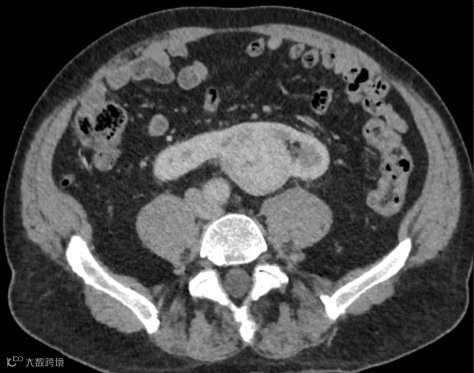

患者,男,60岁,因怀疑主动脉夹层而进行CTA检查,发现马蹄肾,肾峡部可见功能性肾实质,由三条肾动脉供血(箭头)。